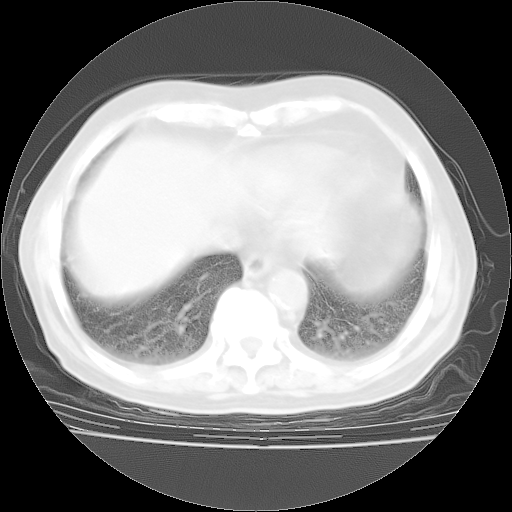

今天部分检查

轻微咳嗽,无痰,(体温正常时)R20次/分,P75次/分,双肺底、腋下可闻及少量捻发音。下肢轻度浮肿。